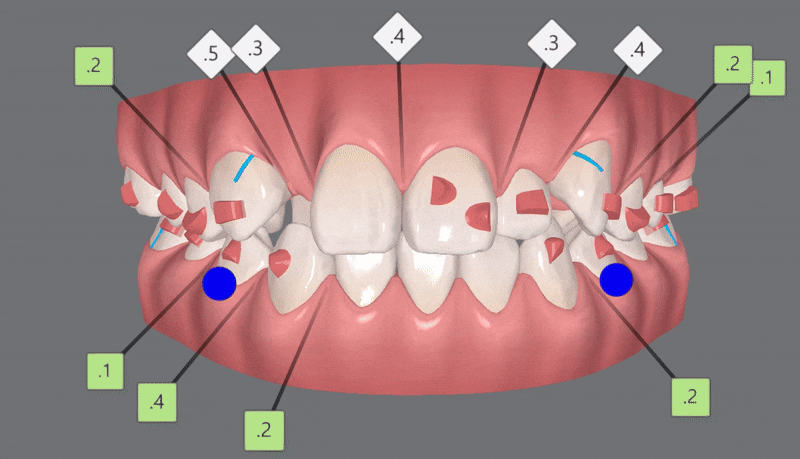

이 환자분은 인비절라인의 옵션 중 하나인

인비절라인 컴프리헨시브 (Invisalign Comprehensive) 옵션으로

세번의 클린체크를 통해 교정치료를 완료하셨습니다.

Invisalign Comprehensive는 부정교합이 비교적 심해 보다 많은 인비절라인 장치가 필요한 경우에 적용됩니다.

1st Clincheck(25개 장치)

2nd Clincheck(26개 장치)

청소년인비절라인 두번째 클린체크 에서는

첫번째 클린체크에서 어태치먼트가 추가되어

이전의 클린체크를 보완해 교정치료의 완성도를 높여 줍니다.

3rd Clincheck(12개 장치)